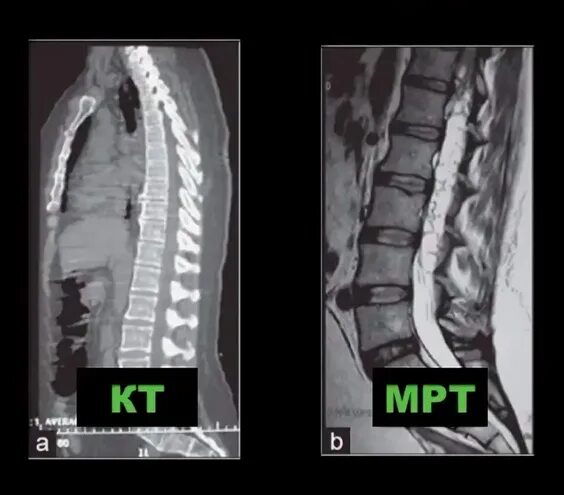

Чем отличается кт от мрт поясничного отдела